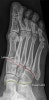

발의 X-ray anatomy

1. Medial column

1) 1st metatarsal

2) Medial cunieform

3) Navicular

4) Talus

2. Middle column

1) 2nd & 3rd metatarsals

2) Middle & lateral cunieforms

3. Lateral column

1) 4th & 5th metatarsals

2) Cuboid

3) Calcaneus

1. Lisfranc joint (forefoot articulation, red line)

2. Chopart joint (hindfoot articulation, yellow line)